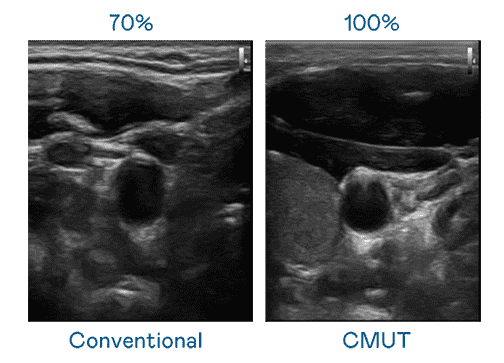

CMUT 技术是一种用电容式微机电元件来产生超音波讯号的技术。。。。与传统 PZT 压电式技术相比,,CMUT 频宽增加 30%,,,更宽频的超音波讯号让影像解析度大幅提升,,是实现高影像品质医疗超音波扫描、、、、促进精准医疗发展的关键技术。。。

大频宽带来超清晰影像

超音波影像的解析度高低,,,首先取决于探头能发出的讯号频宽。。。z6mg·人生就是博 CMUT 可提供高清晰的超音波讯号,,提供高频宽、、高灵敏度、、、、影像纹理细节更高的超音波影像,,协助医护人员缩短影像判读时间及利用精准的医疗影像进行诊断。。